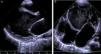

O eletrocardiograma (ECG) mostrou taquiarritmia de complexos estreitos, com frequência cardíaca entre 150‐180bpm, não revertida com adenosina, compatível com taquicardia ventricular. A telerradiografia torácica revelou cardiomegalia (índice cardiotorácico >0,6, Figura 1) e o estudo analítico, elevação das transaminases (TGO 94UI/L, TGP 72UI/L), do BNP (742pg/ml) e hiponatremia (133mEq/L). Os marcadores de necrose miocárdica foram negativos. O ecocardiograma transtorácico (Figura 2 A e B) mostrou dilatação e disfunção sistólica grave do VE (diâmetro telediastólico do VE de 65mm: z‐score+7,8; diâmetro telessistólico do VE de 60mm: z‐score+12,3, fração de ejeção do VE de 20% e fração de encurtamento do VE de 12%). Visualizou‐se trabeculação exuberante e recessos intertrabeculares profundos preenchidos por sangue das paredes lateral e região apical do VE, e a relação entre a espessura da camada não compactada e a espessura da camada compactada foi superior a 2, medido em incidência paraesternal eixo curto, em telessístole (segundo critérios de Jenni et al.).

A: ecocardiograma transtorácico – incidência paraesternal eixo longo – mostra trabéculas proeminentes separadas por recessos profundos na parede lateral do ventrículo esquerdo. B: ecocardiograma transtorácico – incidência apical quatro câmaras – visualiza‐se padrão trabecular da parede lateral e apical do ventrículo esquerdo.